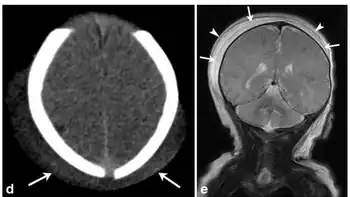

Caput succedaneum is a neonatal condition involving a serosanguinous, subcutaneous, extraperiosteal fluid collection with poorly defined margins caused by the pressure of the presenting part of the scalp against the dilating cervix (tourniquet effect of the cervix) during delivery.

It involves bleeding below the scalp and above the periosteum.[1]